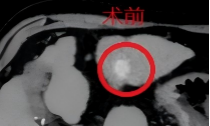

患者为老年女性,既往因腹痛被诊断为肝细胞癌、布-加综合征、肝硬化失代偿期,曾于外院行经导管动脉化疗栓塞术(TACE),长期口服仑伐替尼靶向治疗,近期复查评估肿瘤进展前来就诊。既往无肝炎病史,入院后经腹部增强CT检查确诊为“肝细胞癌(BCLCB期、CNLCIIb期)”,肝左、右叶均有病灶,最大的位于肝右叶,大小约5.2cm×4.8cm,局部浸润。结合患者病情,传统治疗方案中手术切除风险较高,且家属拒绝外科切除治疗。

术后经过保肝、止吐、预防感染等对症治疗,患者仅出现轻微低热(37.6℃)及右上腹隐痛的轻微反应,考虑为栓塞后综合征,经对症处理后已缓解,无严重并发症。术后1个月复查腹部增强CT提示肿瘤内碘化油沉积良好,病灶无明显强化,治疗效果显著。目前患者已顺利出院,将按计划进行后续随访及治疗。